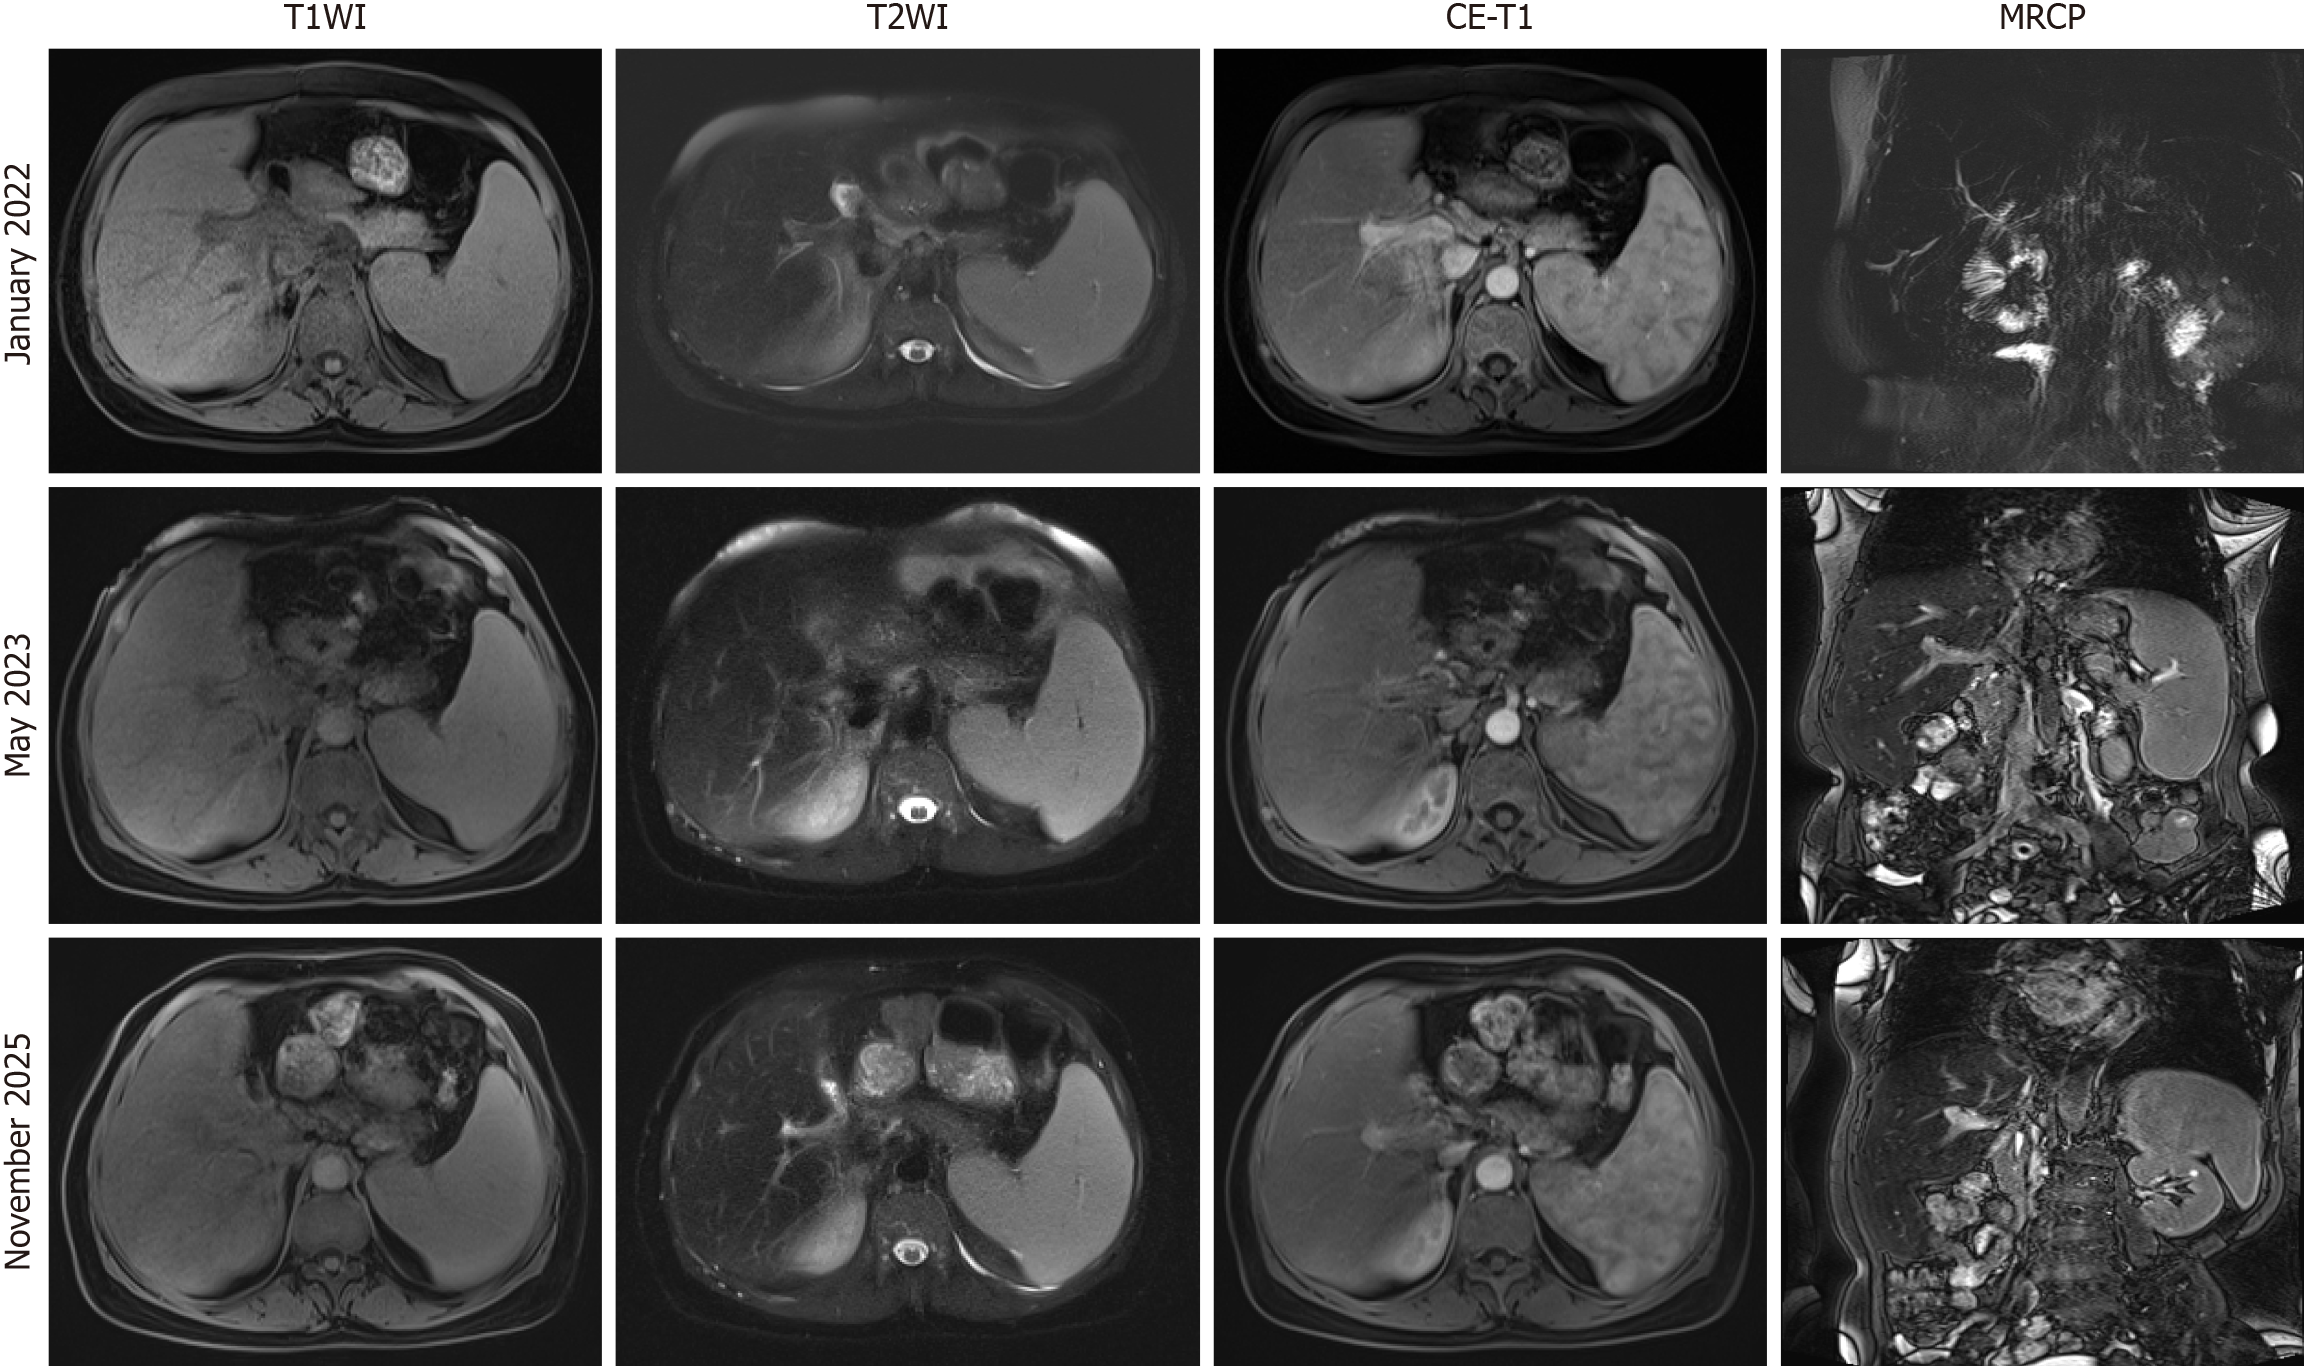

January 2022 magnetic resonance imaging of the upper abdominal (plain scan + contrast) with magnetic resonance cholangiopancreatography showed absence of the left hepatic lobe and gallbladder status post resection, mild intrahepatic bile duct dilation, and abnormal rim-enhancing lesion adjacent to the hepatic hilum in the right lobe with peripheral hyperperfusion, suggestive of inflammatory pathology. Imaging features were consistent with cirrhosis and splenomegaly (Figure 2).

Figure 2 Dynamic evolution of postoperative liver lesions in patients. Upper abdominal magnetic resonance imaging with magnetic resonance cholangiopancreatography (January 2022, May 2023, November 2025): Imaging revealed post-resection absence of the left hepatic lobe and gallbladder, along with mild intrahepatic biliary dilatation. A rim-enhancing lesion with perilesional hyperperfusion was observed adjacent to the right hepatic hilum, consistent with an inflammatory process. Overall features supported cirrhosis and splenomegaly. Follow-up studies (2023, 2025) showed progressive enlargement of the abnormal perfusion area compared to the initial 2022 study. MRCP: Magnetic resonance cholangiopancreatography.

The patient’s condition improved after treatment and was discharged. Post-discharge, the patient was prescribed intermittent norfloxacin for anti-infection therapy and continued ursodeoxycholic acid capsules orally for jaundice management. Follow-up studies (2023, 2025) showed progressive enlargement of the abnormal perfusion area compared to the initial 2022 study (Figure 2).